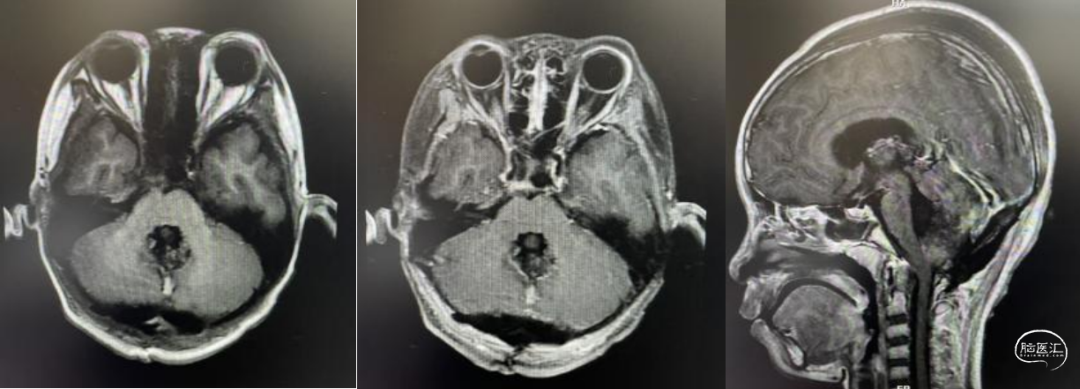

头部CT及CTA检查:小脑蚓部可见3.8*3.7cm的高密度灶,CT值约33-63HU,周围可见低密度带。增强后病灶未见明显强化。四脑室受压,幕上脑室扩张。余双侧脑实质内未见明显异常密度灶,脑沟、脑裂及脑池未见异常,中线结构无移位。颅脑CTA三维成像示:病灶内可见小脑后下动脉穿行其中。双侧颈内动脉颅内段、双侧椎动脉颅内段、基底动脉、双侧后交通动脉、前交通动脉及双侧大脑前、中、后动脉及分支显示好,形态、大小、分布未见异常;未见狭窄、闭塞,未见畸形血管影。